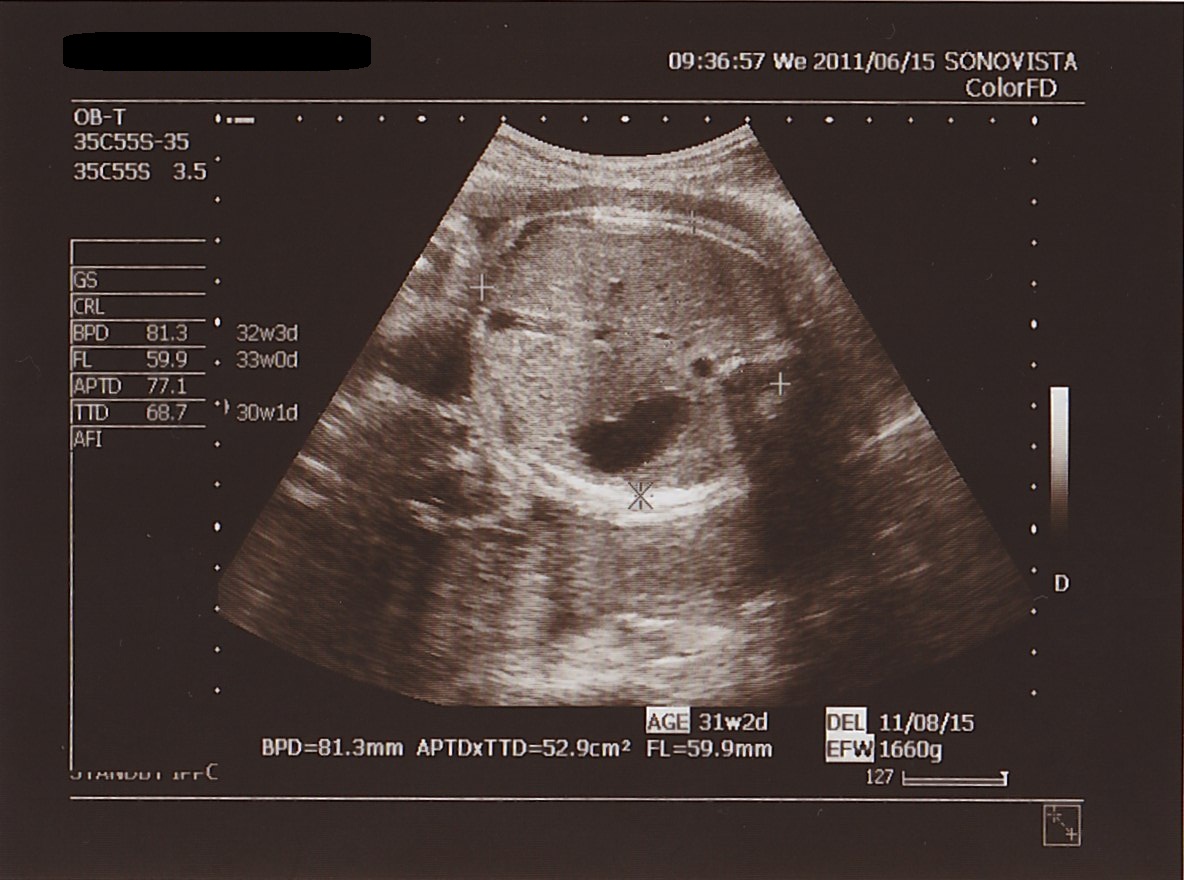

▲ もう エコー写真に 変化はあまり 見られません。

本日の 測定値。

BPD ( 頭の直径 ) : 81.3ミリ

APTD × TTD ( お腹まわり ) : 52.9平方センチメートル

FL ( 太もも骨長 ) : 59.9ミリ

EFW ( 推定体重 ) : 1660グラム

想定週数 : 31w 2d

でした。